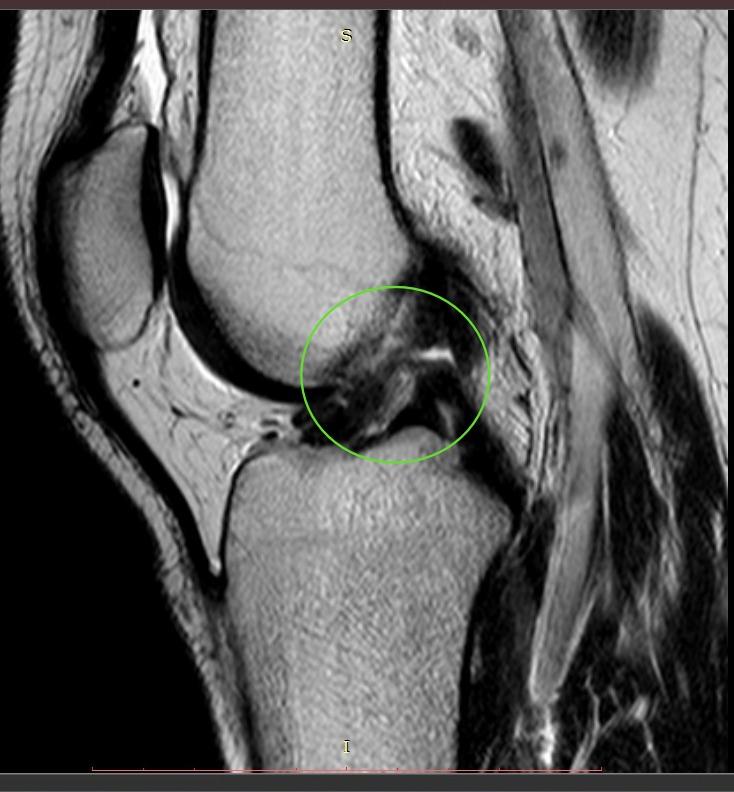

- МРТ левого коленного сустава.

Субтотальный разрыв передней крестообразной связки, частичное повреждение медиальной коллатеральной связки и структур латерального коллатерального комплекса, околокапсулярный разрыв заднего рога медиального мениска.